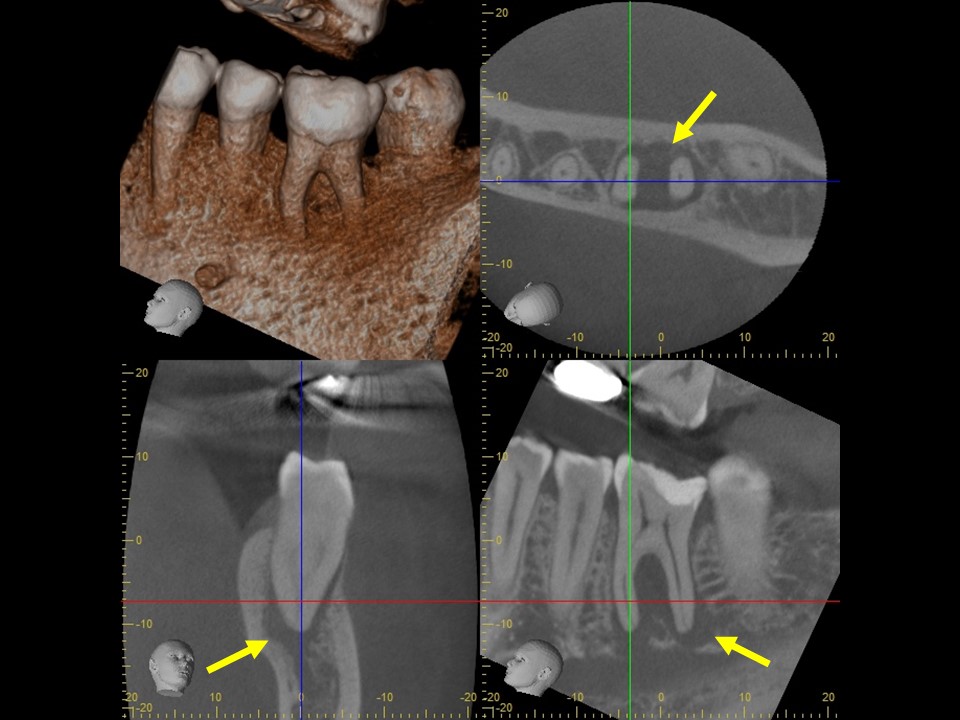

初診時レントゲンおよびCT画像です。根尖部には根尖病変と思われる黒いX線透過像を認めます(矢印)。

歯冠部には、歯髄に近接するレジン充填と思われる白いX線不透過像を認めます。深い虫歯治療後に歯髄壊死を生じたと推察されます。